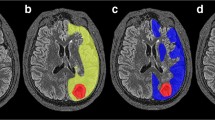

The PCT CBF ratios showing the best correlation with PET H2 15O ratios (slope = 0.842, intercept = 0.220, R 2 = 0.797, p < 0.001) were calculated using a combined AIF, i.e., a dedicated AIF for each territory (ACA AIF for ACA territory, right MCA AIF for right MCA territory, left MCA AIF for left MCA territory; Fig. 1).

This comparison of PCT and O15O/H2 15O PET in a small retrospective series of six patients with carotid occlusion showed that using a dedicated AIF for each territory provides the best agreement with PET data in patients with carotid occlusion. This is in contrast with PCT datasets obtained in patients with acute stroke, where a single AIF, typically selected in the ACA, is sufficient [9]. In patients with carotid occlusion, selecting such a single AIF leads to overestimated MTT values and underestimated CBF values in the vascular territory dependent on the occluded carotid artery because of the additional delay in arrival time and the dispersion of the contrast agent during its transit to the tissue of interest, reflecting an increase in density, length, and importance of the collateral pathways supplying the brain region at risk [10–12]. A dedicated AIF approach minimizes the delay and dispersion of the contrast bolus between the area of measurement and the tissue of interest, and has the potential advantage of better reflecting the true hemodynamics of the ischemic lesions by taking into account the effects of collateral circulation to the ischemic tissue [12, 13]. The practical, clinical importance of a dedicated AIF selection for the processing of PCT studies obtained in patients with chronic cerebrovascular disease, such as carotid occlusion or EC–IC bypass or a giant carotid aneurysm, is illustrated in Fig. 3.

a Patient with a right carotid artery occlusion (arrows) demonstrated on a volume-rendering image of a CT angiogram viewed from above. b When processed using a single arterial input function (AIF; left column) selected in the anterior cerebral artery (ACA), PCT dataset obtained in the same patient demonstrates significantly asymmetric mean transit time (MTT) and cerebral blood flow (CBF) values, with increased MTT and low CBF on the side of the carotid artery occlusion, suggesting ischemia within the right hemisphere. When processed using each vascular territory’s own AIF (middle column), the same PCT dataset shows almost symmetric MTT and CBF values, which are in agreement with PET H2 15O (third column). Cerebral blood volume (CBV) values are unaffected by the selection of the AIF